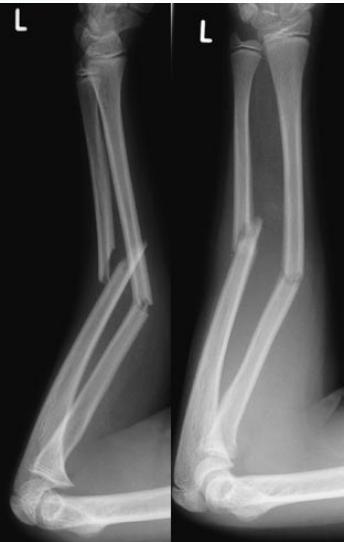

Unstable Fractures

- Both bones at same level (ex: forearm)

- Oblique fractures

- Comminuted fractures (difficult in healing)